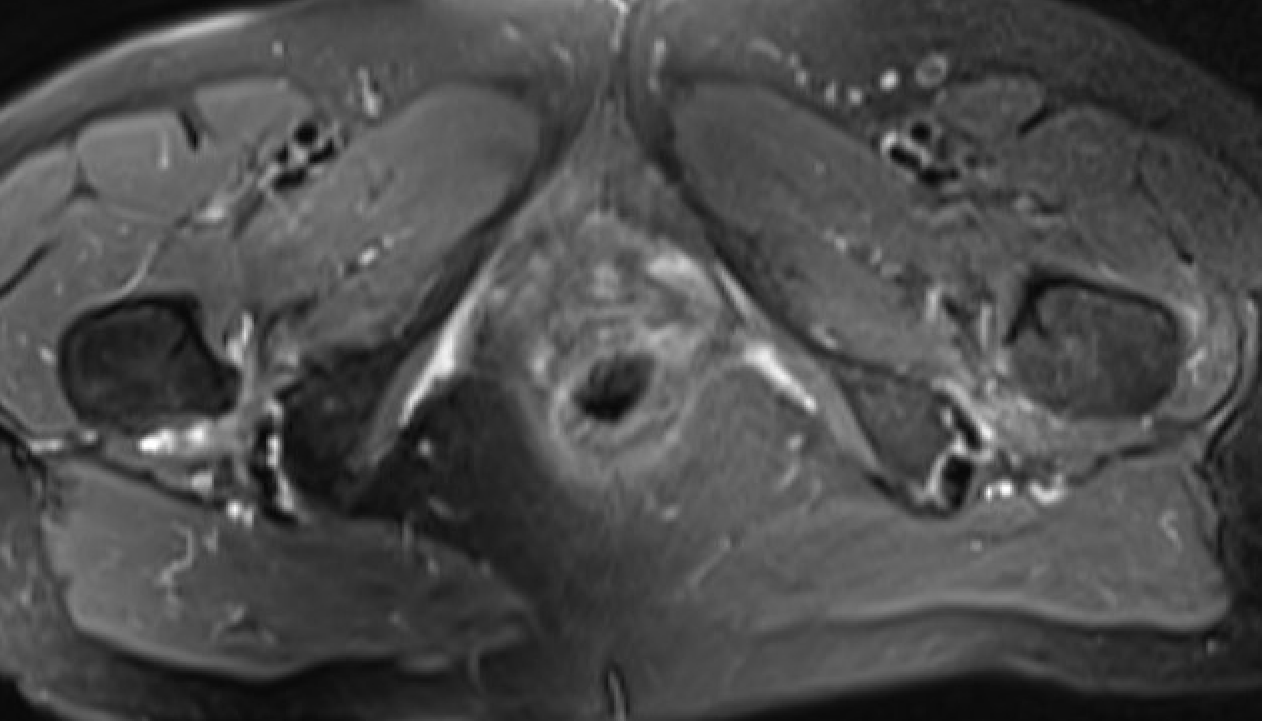

MRI

Reduced ischiofemoral space - distance between the lesser trochanter and the ischial tuberosity

Reduced quadratus femoris space - distance between hamstring tendon and iliopsoas

Inflammation / edema in quadratus femoris +/- fatty degeneration

Singer et al Skeletal Radiol 2015

- systematic review of 190 hip MRI of patients with ischiofemoral impingement

- compared to controls

- ischiofemoral space < 15 mm: sensitivity  77%, specificity 81%, accuracy 78%

- ischiofemoral space < 10 mm: sensitivity 79%, specificity 74%, accuracy 77%.